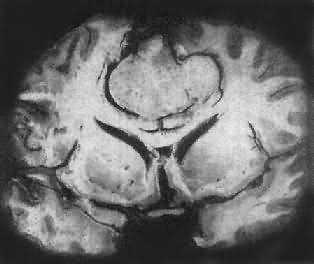

图16-26 髓母细胞瘤 瘤细胞较小,着色深,密集排列,有菊形团形成 髓母细胞瘤恶性程度高,预后差。 (三)脑膜瘤 脑膜瘤(meningioma)可来源于脑膜的各组成成分如蛛网膜细胞,纤维母细胞或血管,其中多数来源于蛛网膜颗粒中的蛛网膜细胞。本瘤大多生长缓慢,良性类型可完全无症状,在70岁以上老人的尸检中,发现无症状的脑膜瘤不在少数,无症状脑膜瘤占颅内肿瘤的14%。脑膜瘤患者多为40~50岁中年人,女性较男性多。 肿瘤的好发部位与蛛网膜颗粒所在部位相同,常见于上矢状窦旁大脑镰两侧,蝶骨嵴,嗅沟,小脑脑桥角;在脊髓则以胸段为多见,一般颅内脑膜瘤较脊髓脑膜瘤多2倍。 肉眼观,肿瘤呈球形,分叶状或不规则形,质实或硬,边界清楚,周围脑组织受压成凹陷切迹(图16-27)。少数肿瘤呈斑块状覆盖较广泛区域,甚至整个脑半球,称为斑块型脑膜瘤。肿瘤质地硬,切面灰白色,呈颗粒状、条索旋涡状,有的质地似砂砾样,乃由于有多量砂粒体存在。

图16-27 脑膜瘤 于大脑两半球间有一近似球形肿瘤,边界清楚,周围脑组织受压萎缩 由于脑膜瘤的组织来源复杂,其组织学图像也可呈现下列基本类型: (1)脑膜细胞型(融合细胞型):瘤细胞胞浆丰富,边界不清楚,胞核椭圆形,细胞排列呈分叶状或旋涡状,为纤维间质条索所分隔。 (2)纤维细胞型:瘤细胞呈长梭形,排列成致密的交织束状结构,其间有网状纤维及胶原纤维,有时胞核呈栅状排列。 (3)过度(混合)型:脑膜细胞与纤维细胞混合,排列成分叶状,中央为脑膜细胞,周围为纤维细胞,常形成旋涡状结构(图16-28),其中常包含有同心层状结构的砂粒体,乃变性肿瘤细胞及钙盐沉积。肿瘤质地硬,似砂砾状。